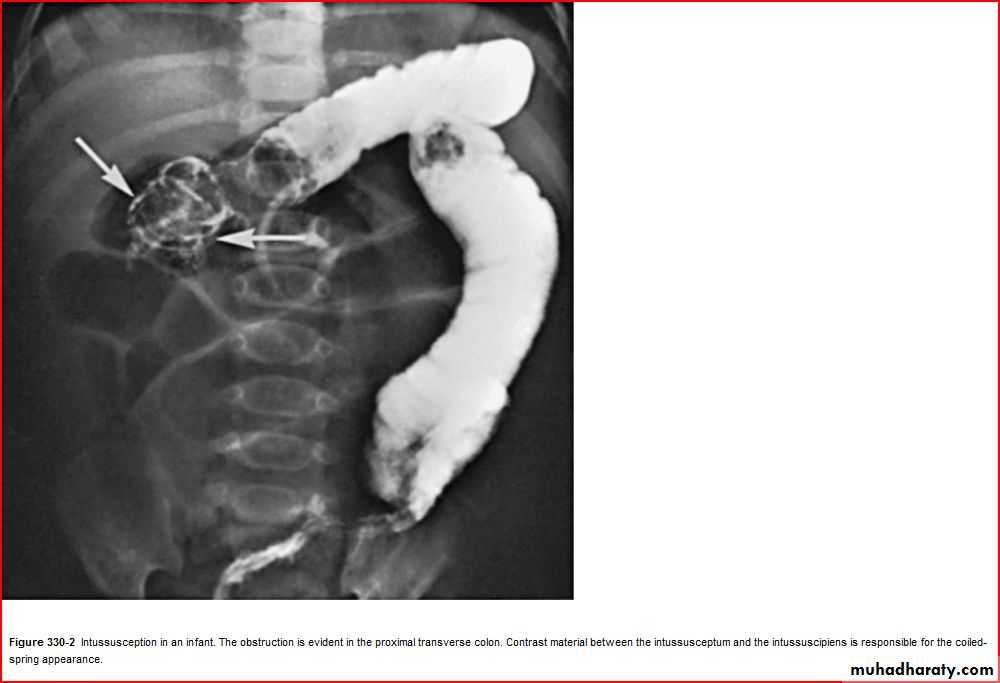

( coil spring sign )Coil spring sign intussusseption

3 signs >> current jelly stool

Suscage mass

Prolapse of the mass theough rectum

Current jelly stool intussuception

Intussuception